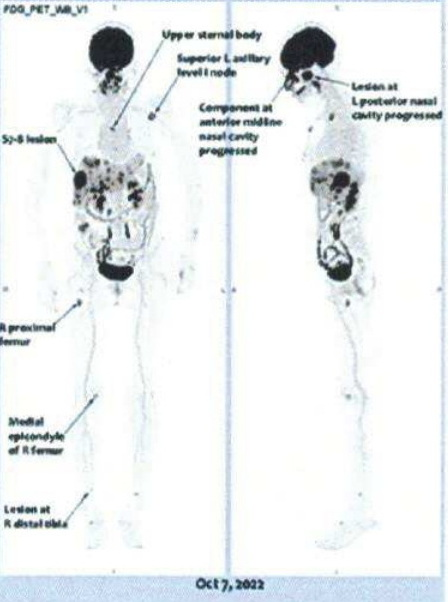

In the routine treatment at Hong Kong Sanatorium & Hospital on 7th Oct., 2022.